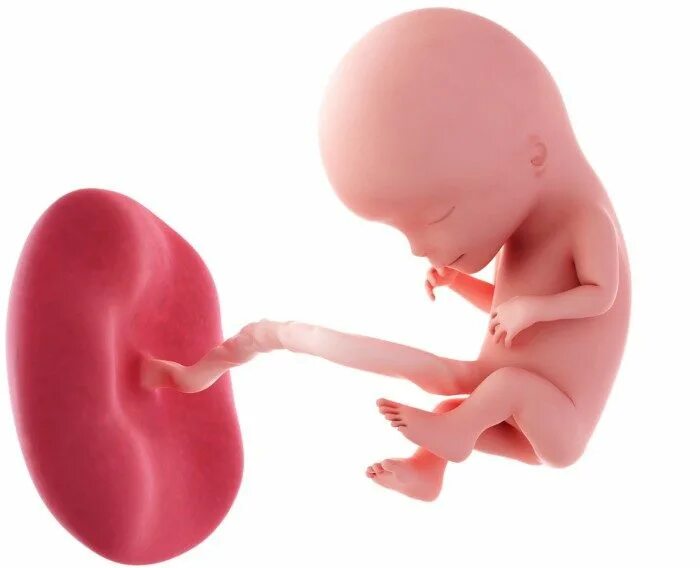

14 неделя ощущение